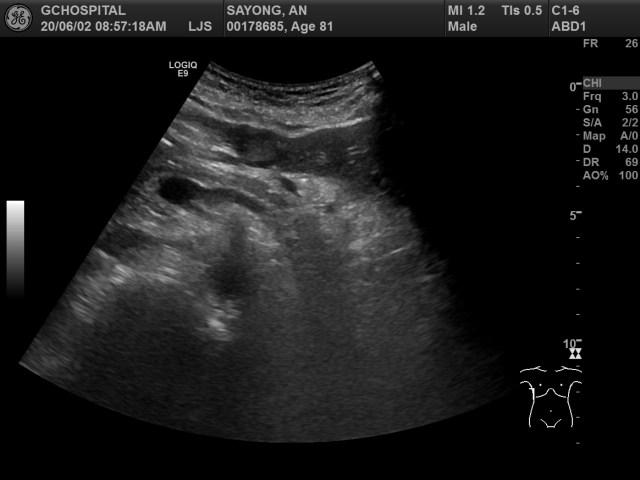

앞서 영상에서는 주파수가 4MHz였고, 포커스도 비교적 화면의 가운데 부분에 맞추어져 있었기 때문에, 좀 더 깊은 곳을 확인하기 위해 주파수를 3MHz로 낮추고 포커스도 최대한 깊은 곳을 볼 수 있게 맞추었습니다. 이렇게 해도 CT영상에서 보이던 췌장꼬리주변의 종괴는 전혀 보이지 않습니다.

이번에는 탐촉자를 왼쪽 옆구리쪽에 대어서 비장 근처를 확인해보았습니다. splenic hilum 근처에 위치한 종괴와, 바로 밑에 연결되있는 췌장 꼬리를 확인할 수 있습니다. CT에서는 확실하게 구분되지 않았던 비장과 종괴 사이의 경계는 비교적 뚜렷하게 구분이 되어있고, 췌장 꼬리부위와 종괴가 전혀 구분되지 않은 것을 확인할 수 있습니다. 해당 종괴는 췌장 꼬리부위에서 발생한 악성종양으로 보입니다.